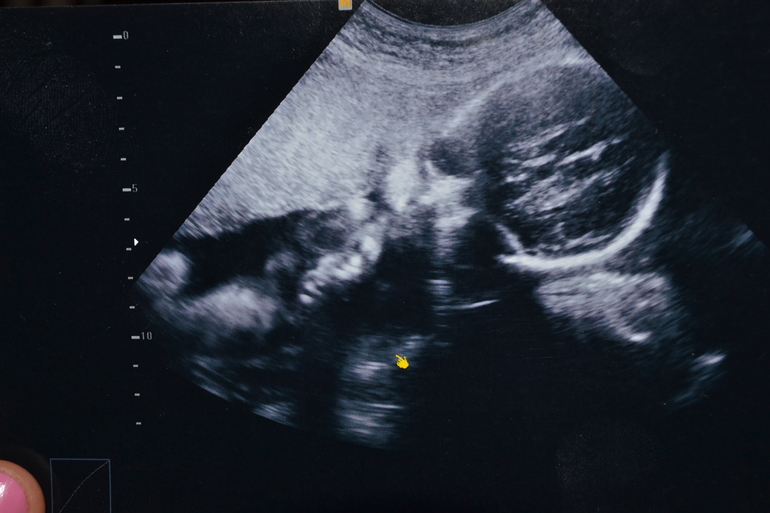

20 неделя

Вроде 2 однотипные фотки, но я всматриваюсь в каждый миллиметр и вижу разницу, на первой щечки надутые и как буд-то палец во рту, а на второй втянутые